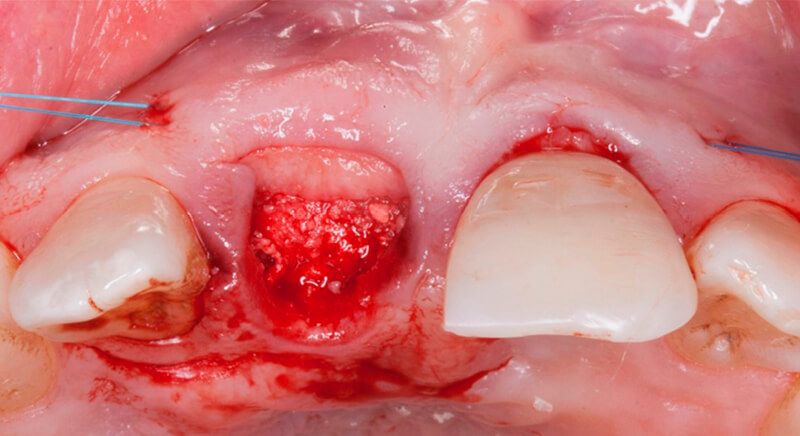

The socket was filled with a xenograft after the extraction and a graft of connective tissue was placed in the vestibular area of the two upper central incisors.

The tissue with epithelium was taken from the palate and de-epithelialized outside of the mouth. This obtains a lamina propria graft with better density and quality than if it were obtained with a single incision to the palate.